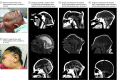

Objective: To describe the clinical features and imaging findings in 24 patients with congenital Zika syndrome (CZS) who developed hydrocephalus.

Results: This multicenter cohort included 308 patients with CZS; 24 consecutive children were enrolled in this study. These children were aged between 3 to 18 months, and 13 of 24 (54%) were female. All patients presented with at least 1 positive test result for anti-Zika antibodies in cerebrospinal fluid or serum and had classic signs of CZS. At the time of hydrocephalus diagnosis, only 14 of 24 patients (58%) had symptoms and signs suggestive of hydrocephalus (mainly worsening seizures, vomiting, irritability, and/or sudden increase of head circumference percentile). Two of 24 patients (8%) had no symptoms suggestive of hydrocephalus but were found to have reduced brain volume on repeated imaging. Cerebellar or brainstem hypoplasia on baseline imaging were found in 18 of 23 patients (78%). At the second computed tomographic scan, all patients showed a marked increase of ventricular volume, compatible with communicating hydrocephalus, and reduction of brain tissue that was visibly worse than on baseline imaging for the 23 patients with repeated scans.